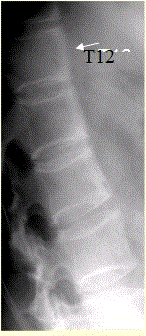

问题 患者男,35岁,外伤后行腰椎CR检查,结果如下图。 观察所给出的CT图像(下图),你的判断是

选项 A.右侧椎肋关节面骨侵蚀 B.椎体前缘骨炎 C.椎体前缘仅仅表现为轻度骨质增生 D.骶髂关节未见异常改变 E.骶髂关节面毛糙 F.骶髂关节间隙模糊

答案 ABEF